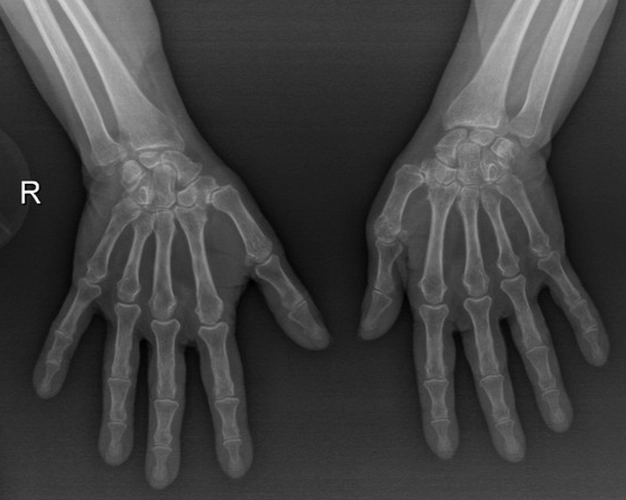

Muayene:Sol omuz: Flex: 0-70°, Abd: 0-70°, İstirahatte VAS: 0, Hareket ile VAS:1-2, GYA’de bağımsız. Sistemik tutulum ve organ tutulumu yok. Diğer fizik muayene doğal ellerde deformite yok.

Resim 3TARTIŞMA VE SONUÇ

Ön tanıda romatoid artrite bağlı eklem tutulumu, avasküler nekroz, Charcot eklemi (periferik nöropati- servikal radikülopati?) olasılıkları tartışıldı. Hastanın ileri derecedeki eklem kısıtlılığı ve buna bağlı gelişen omuz çevresi kaslarda atrofisi olması sebebi ile artroplastiden fayda görebileceği öngörüldü.